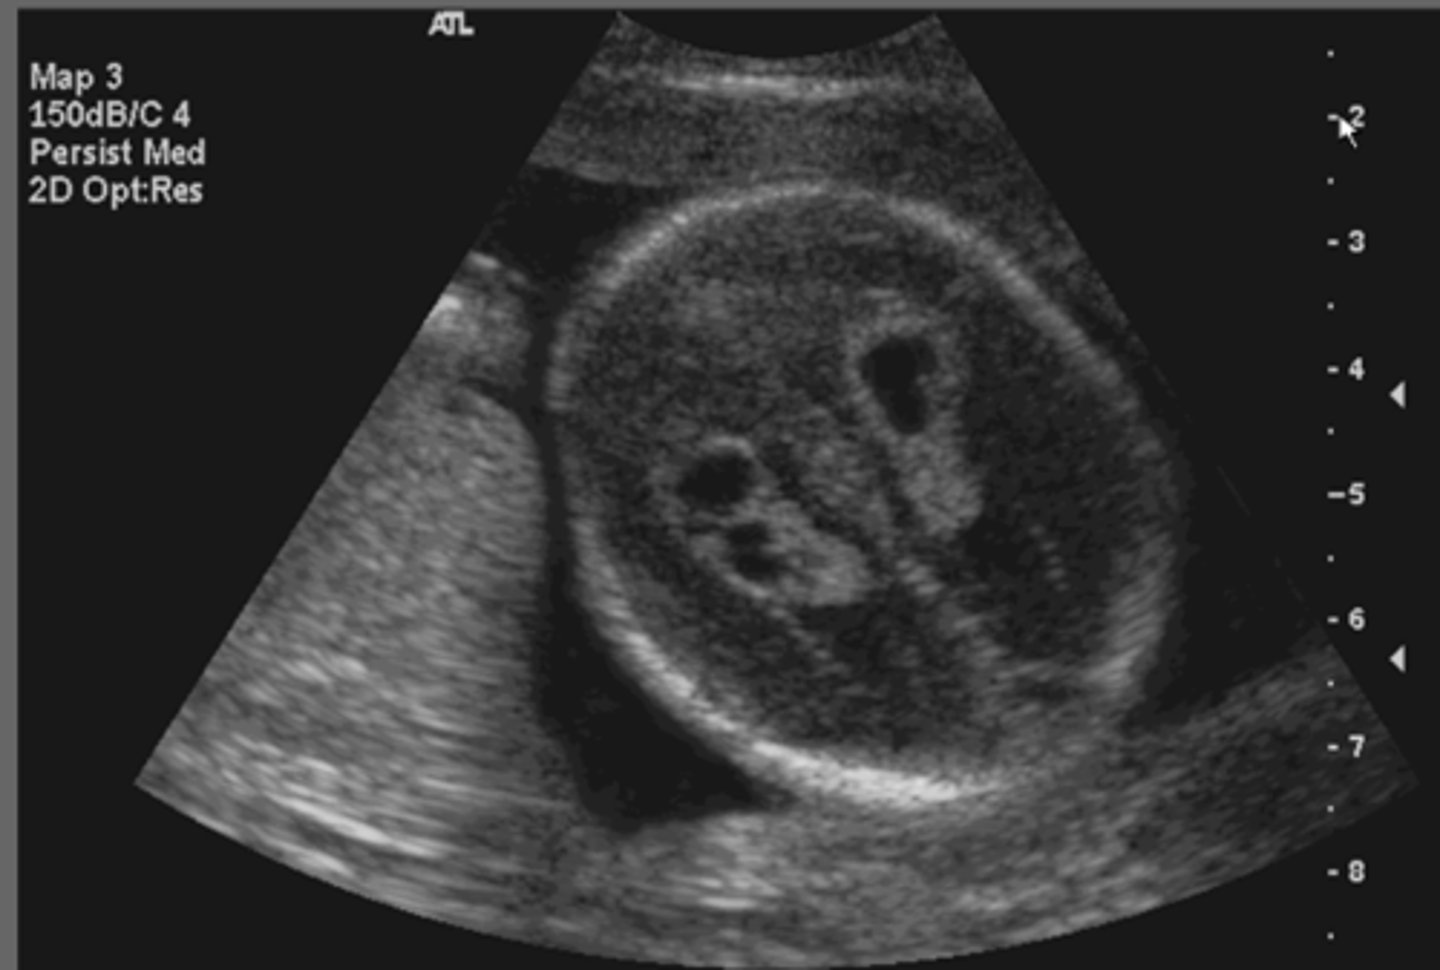

Alobar Holoprosencephaly

Single ventricle

Fusion of thalamus